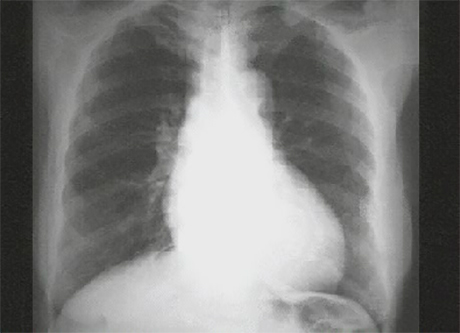

Your choice: Left ventricular enlargement and dilated aorta PA

This chest X ray show left ventricular enlargement and a dilated aorta. This PA view demonstrates cardiomegaly, as evidenced by a cardiothoracic ratio greater than fifty percent. Note also the increased inferolateral cardiac border that is consistent with left ventricular enlargement due to volume overload. The ascending, transverse and descending aortic shadows are also prominent.